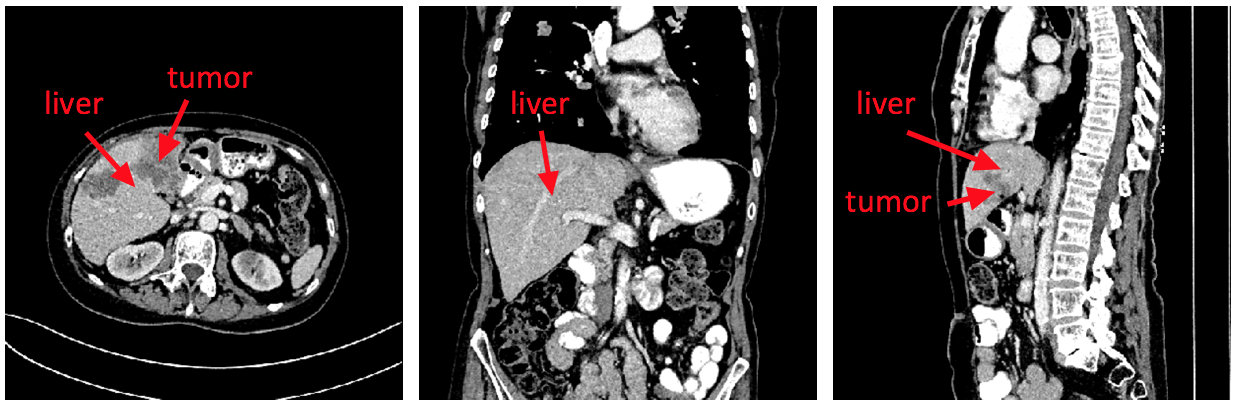

Figure 5 The examples of CT images in the transverse plane, coronalplane,and sagittal plane respectively